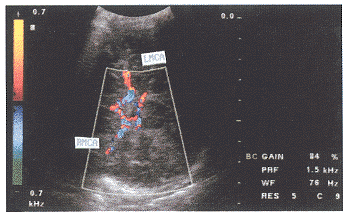

MCA、PCA的血流测定:从颞侧作水平扫查,此时超声声束与血管夹角较小。取样容积放在主干进行取样。显示大脑动脉环,探查MCA、PCA。彩色多普勒显示,大脑环动脉环上方,及下方分别可见左右两侧的彩色血流(图3、4)。左侧探测,左侧MCA、PCA呈红色血流,多普勒频谱为正向,右侧MCA、PCA呈蓝色血流。大脑后动脉,位于Will环后方,左侧呈红色血流,右侧呈蓝色血流,多普勒频谱为负向。探头改变方向,血流及频谱则反之(图5、6)。

图3 MCA彩色血流

图4 PCA彩色血流